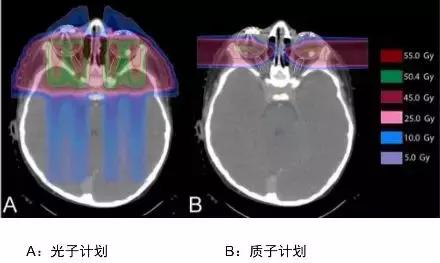

标准放射治疗的目标为全脑加上全脊椎,治疗涵括范围较大。传统X光放疗在治疗全脑全脊椎的同时无法避免照到腹部、骨盆腔器官,甚至可能造成放射线暴露器官的次发性肿瘤产生。相较之下,质子放疗能有效侷限放射剂量于目标组织,而不波及非治疗目标的其他器官。此外,在小儿小脑髓母细胞瘤的放射线疗程中,为了尽量消灭所有癌细胞,会于病童后颅窝额外加强放射,传统X光放疗连双侧耳蜗都会受到照射剂量,会造成小朋友后续听力减弱;若使用质子治疗,则对耳蜗的放射剂量能够趋近于零,病童放疗之后的听力得以保存。

这是头颈部肿瘤剂量分布图比较,我们明显能看到两者的差异,常规放疗蓝色区域很大,说明射线对病灶周边的正常组织有不可避免的损害,质子放疗可以减少咽喉和口腔部位的放疗损伤,降低发生口角炎、口腔炎、吞咽困难、口干的发生率。